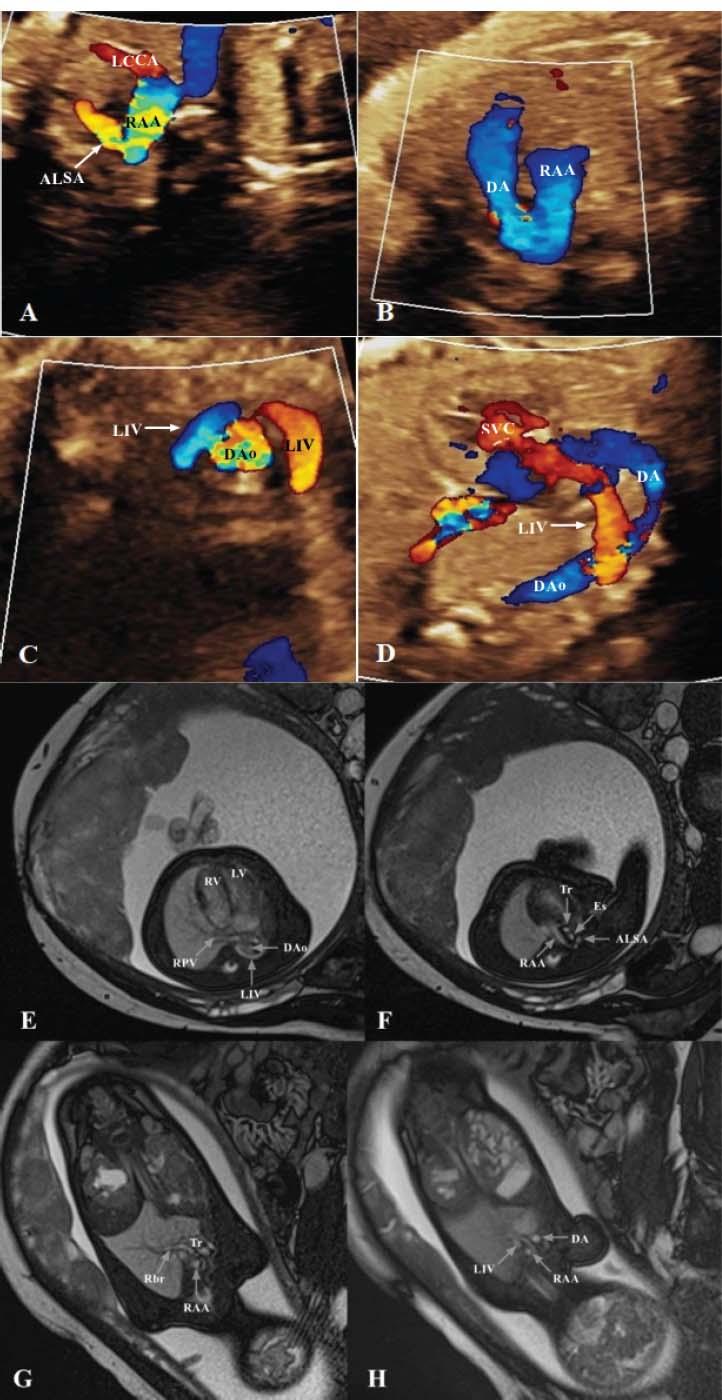

Figure 1

Figure 2

Figure 3